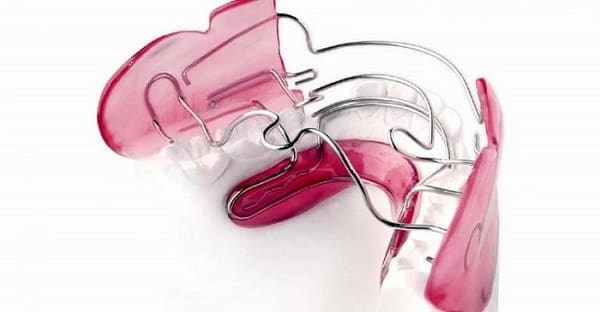

دستگاههای فانکشنالی که معمولاً مورد استفاده قرار میگیرند

بیوناتور

“بیوناتور” اصطلاح عمومی برای خانواده ای از وسایل قابل جابجایی است که برای جابجایی فک پایین به حالت جلوتر استفاده میشوند. این حالت معمولاً زمانی مطلوب است که دندانهای بالا به نسبت دندانهای پایین خیلی جلوتر قرار میگیرند، در نتیجه نوعی مال اکلوژن (مشکل نیش) به شما اضافه میشود. مانند یک نگهدارنده، بیوناتور قابل جابجایی است و با استفاده از سیم به دندانهای فوقانی نگه داشته میشود. بیوناتور ساخته شده از آکریلیک (پلاستیک)، به طور کلی دارای یک قسمت فوقانی است که در پشت دندانهای جلویی قرار دارد و قسمت پایینی که با دندانهای زیر تماس دارد. هنگامی که فک بسته است، شکل شیب قسمت پایین باعث میشود دندانهای پایین به سمت جلو حرکت کند. با گذشت زمان، این موقعیت یابی مجدد باعث ایجاد تغییرات اسکلتی و عضلانی در فک میشود که میتواند نیش دندانی را در تراز بهتری قرار دهد.

ابزار ارتودنسی تویین بلاک (Twin Block)

ارتودنسی تویین بلاک از لحاظ عملکردی با بیوناتور مشابه است، اما به جای یک قطعه از دو قطعه ساخته میشود. این امر باعث میشود تا ارتودنسی زیاد بزرگ نباشد و راحت تر قابل استفاده شود. نیمه بالایی ارتودنسی تویین بلاک توسط سیم های قابل انعطاف به دندانهای فوقانی متصل و نگه داشته میشود و با یک روش مشابه نیمه پایینی به دندانهای پایینی متصل میشوند. هنگامی که فکها به هم بسته شدهاند، دو نیمه دستگاه جمع میشوند و سطوح شیب دار در محل اتصال باعث میشود که فک پایین به سمت جلو حرکت کند.

ارتودنسی تویین بلاک معمولاً قابل جابجایی هستند، اما در صورت لزوم میتوانند در جای خود ثابت شوند. آنها به گونه ای طراحی شده اند که 24 ساعت در روز پوشیده شوند. این وسایل همه کاره میتوانند به گونه ای طراحی شوند که شامل مؤلفههایی مانند دستگاههای انبساط، بست و فنر باشند، بنابراین میتوان آنها را برای نیازهای شخصی تنظیم کرد.